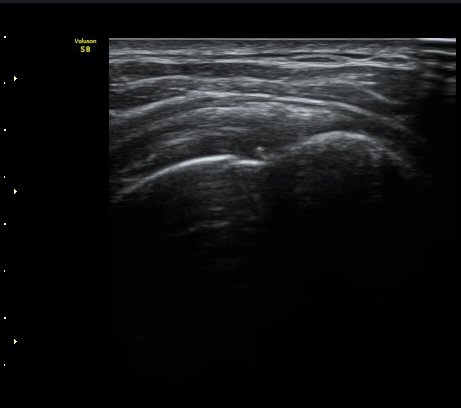

ÃÊÀ½ÆÄ °Ë»ç

ÀÌµÎ¹Ú±Ù°Ç È¾´Ü¸é°Ë»ç¿¡¼­ ƯÀÌ ¼Ò°ßÀ» º¸ÀÌÁö ¾ÊÀ½(»çÁø 1, 2).